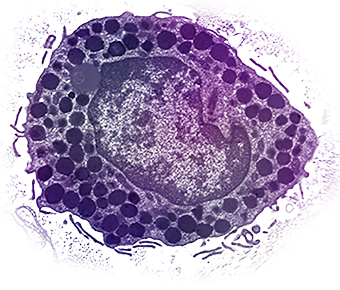

Macrophages

PHAGOCYTES AND CYTOKINE SOURCES

Long-lived phagocytes that engulf and digest microbes and debris

Act as antigen-presenting cells (APCs) and secrete cytokines (like IL-1, TNF) to orchestrate inflammation.

Can be tissue-resident or monocyte-derived (arise from monocytes that invade tissue in response to infection/cancer)